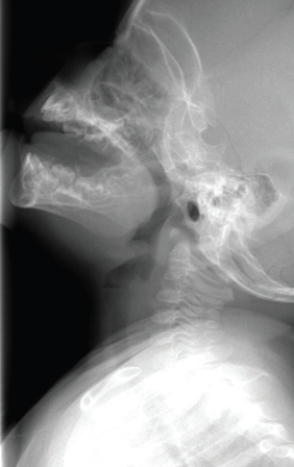

This image shows a child with: